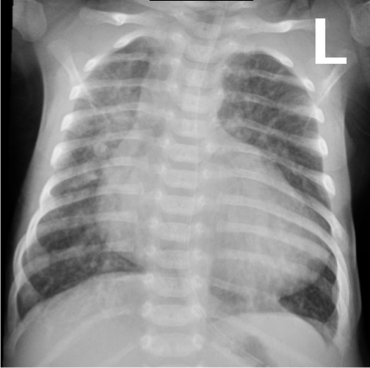

Imaging

- Small to N cardiac silhouette

- Decrease pulmonary vasculature